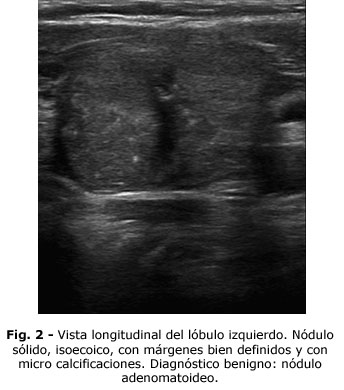

2. Nódulos sólidos o predominantemente sólidos, hiperecoicos

o isoecoicos con microcalcificaciones (n = 4, Fig. 2).